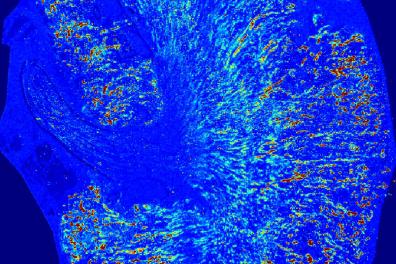

La plateforme Paterson regroupe différents spectromètres de masse destinés à l’analyse du contenu isotopique de divers échantillons, notamment environnementaux ou biologiques, comme cette « coupe » par ablation laser de rein de souris (la concentration en ions uranium 238 étant croissante du bleu au rouge).

Pourquoi s’intéresser à ces sources de pollution ? Parce que les isotopes radioactifs ne sont pas totalement inoffensifs pour la santé. Cette toxicité est l’objet de la thèse de Laurie de Castro, menée sous la direction de Yann Gueguen, chercheur en toxicologie au Laboratoire de recherche en radiochimie, spéciation et imagerie (LRSI) implanté à Fontenay-aux-Roses. Partant du constat que, dans l’organisme, l’uranium s’accumule préférentiellement dans les reins et les os, elle étudie ses effets potentiellement cancérigènes à l’aide de modèles de souris génétiquement modifiées. Celles-ci sont prédisposées à développer un cancer du rein. « Les spectromètres révèlent la distribution globale de l’uranium dans les tissus, puis sa microdistribution. L’objectif in fine est d’identifier les mécanismes cellulaires de cancérogenèse », indique la doctorante. Ses travaux sont en cours, mais des résultats préliminaires ont d’abord validé les conditions d’études choisies. Les chercheurs indiquent avoir également « mesuré la répartition de l’uranium dans les organes en fonction du temps et de la dose. » Préalable indispensable pour l’étude de la cancérogenèse rénale, ils ont aussi déterminé le seuil à partir duquel l’uranium devient néphrotoxique, après exposition répétée par les voies aériennes supérieures pour mimer une inhalation.